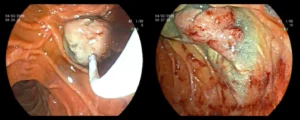

Πολύποδας παχέος εντέρου

![]()